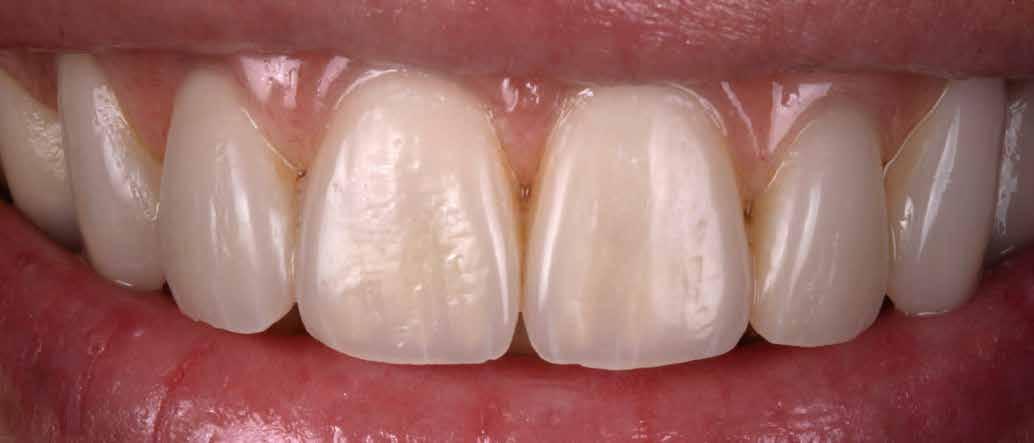

Interdiszciplináris fogászati kezelés myofunkcionális készülék, alignerek és protetikai ellátás alkalmazásával

MED. DENT Abradált frontfogakkal rendelkező felnőtt páciens interdiszciplináris kezelése